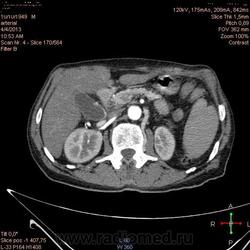

Здравствуйте, коллеги.Помогите разобраться.Пациент 1949 г беспокоять боли в животе , отсутствие аппетита, похудание .За неделю пожелтел, ослаблен.Нужно исключит кацер головки подж.железы.Анализы сегодня сдал еще не готовы.УЗИ зак увеличение л\узлов у ворот печени.Образов головки подж.железы ?На КТ жировой гепатоз.вроде головка подж железы не увеличены.

Мне надо исключить или поставить образование головки подж.железы.Хирурги ждут заключение, хотять оперировать.

Даже если вы пропустили малый рак панкреас, пациент умер не из-за него - желтуха не механическая, а, вероятней, паренхиматозная.